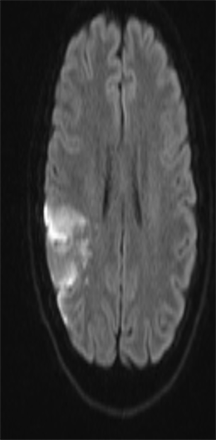

We report the case of a 24 years old female patient with vascular risk factors such as active smoking of 8 pack-years and a combined estrogen/progestin contraceptive. Her family history included an uncle with heterozygote factor V Leyden mutation. Presenting symptoms included a general feeling of being unwell without loss of consciousness, a mild dysarthria event and a fast-regressive left hemiparesis, with persistent weakness particularly in the left hand. Note that she had no headache. She was immediately admitted to the emergency department for thrombolysis. Brain scan and computed tomography (CT) Angiography of supra-aortic trunks completed with Magnetic Resonance Angiography (MRA) revealed ischemic stroke in the right sylvian territory affecting the parietal lobe, with no hemorrhagic conversion and no arterial occlusion [Figure 1]. Alternatively, magnetic resonance imaging (MRI) showed a vascular anatomic variant such as agenesis of the right internal carotid artery (ICA) with the right middle cerebral artery (MCA) fed through a dilated posterior communicating artery (PCOM) arising from the basilar artery [Figure 2; Figure 3]. CT scans at skull base level with bone settings showed absence of the right carotid canal, thus confirming agenesis, for which arteriography was requested [Figure 4]. Arteriography showed an operative circle of Willis, a MCA supplied by an enlarged right

Figure 1. Right Sylvian ischemic stroke. MRI of 24-year-old female patient (DAX hospital center).